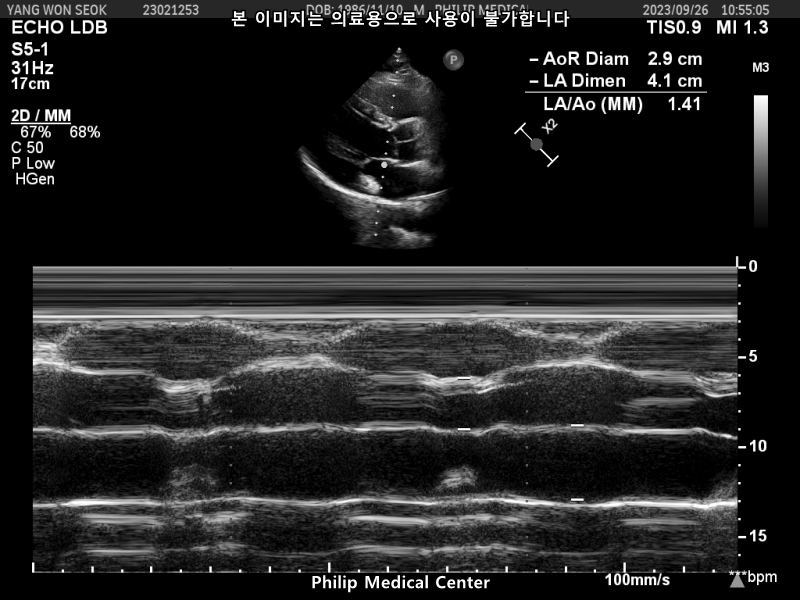

심장초음파는 경미한 폐동맥 판막역류소견과 심전도 검사결과 비특이적 ST-T파 이상소견이있었습니다.

• 2번 째 사진